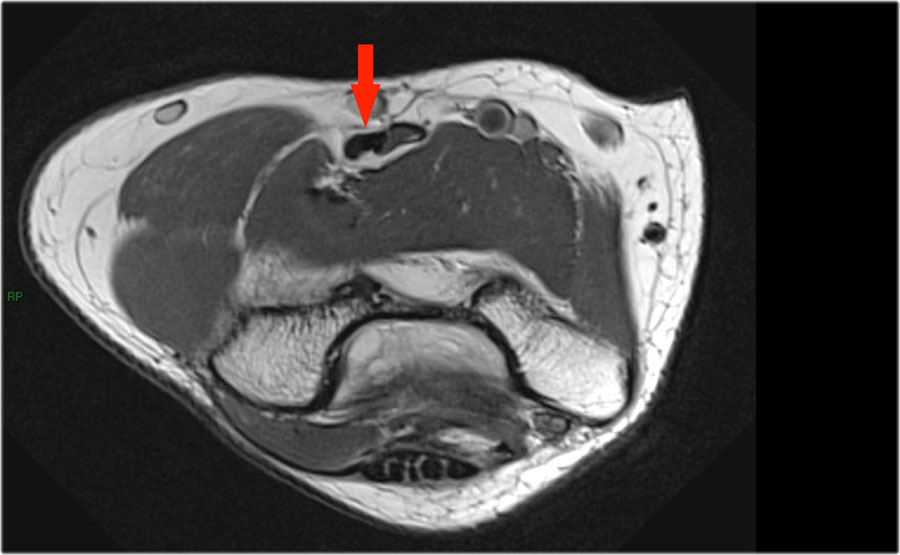

Những hình ảnh này của một nam giới 23 tuổi bị ngã chống tay khi đang trượt ván hai tuần trước.

Khi khám lâm sàng, ghi nhận giảm biên độ vận động khớp khuỷu và đau khi ấn dọc theo mặt ngoài.

Cấu trúc nào nằm phía sau chỏm quay trên hình ảnh cắt ngang?

Sagittal view:

- Một lần nữa, hình ảnh đặc trưng của phù tủy xương thường gặp trong trật khớp khuỷu tay ra sau với vết dập ở phía trước của chỏm xương quay (mũi tên đỏ) và ở phía sau của chỏm con xương cánh tay.

- Chỏm quay phải đã va chạm vào phần sau của chỏm con xương cánh tay.

Cấu trúc phía sau chỏm quay là dây chằng vòng.

Nó không đều và dày lên do hậu quả của trật khớp ra sau.